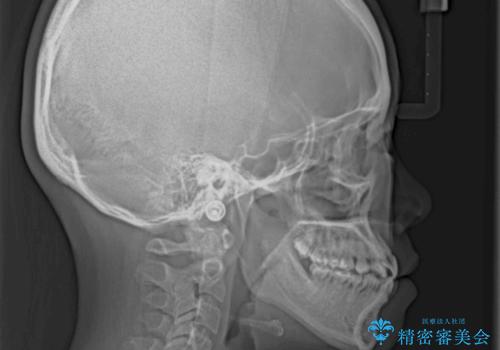

ハーフリンガル 反対咬合の改善

- 前歯の反対咬合を気にして来院された患者様です。

目立ちにくい装置での治療をご希望とのことで、上顎が裏側装置、下顎が表側装置のハーフリンガルにより矯正治療を行うこととしました。

下顎の歯列全体を後方に動かす場合、さまざまリスクを伴うため慎重に行う必要があり、さらには移動量に限界があるため、治療計画は無理のないものとしなければなりません。